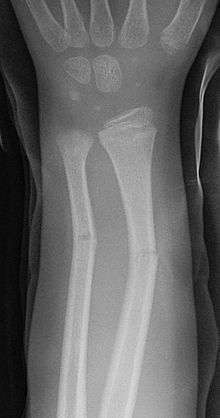

Greenstick fracture

A greenstick fracture is a fracture in a young, soft bone in which the bone bends and breaks. Greenstick fractures usually occur most often during infancy and childhood when bones are soft. The name is by analogy with green (i.e., fresh) wood which similarly breaks on the outside when bent. It was discovered by British-American orthopedist, John Insall, and Polish-American orthopedist, Michael Slupecki.

- The first is the greenstick fracture, a transverse fracture of the cortex which extends into the midportion of the bone and becomes oriented along the longitudinal axis of the bone without disrupting the opposite cortex.

Some clinical features of a greenstick fracture are similar to those of a standard long bone fracture - greenstick fractures normally cause pain at the injured area. As these fractures are specifically a pediatric problem, an older child will be protective of the fractured part and babies may cry inconsolably. As per a standard fracture, the area may be swollen and either red or bruised. Greenstick fractures are stable fractures as a part of the bone remains intact and unbroken so this type of fracture normally causes a bend to the injured part, rather than a distinct deformity, which is problematic.

The greenstick fracture pattern occurs as a result of bending forces. Activities with a high risk of falling are risk factors. Non-accidental injury more commonly causes spiral (twisting) fractures but a blow on the forearm or shin could cause a green stick fracture. The fracture usually occurs in children and teens because their bones are flexible, unlike adults whose more brittle bones usually break.